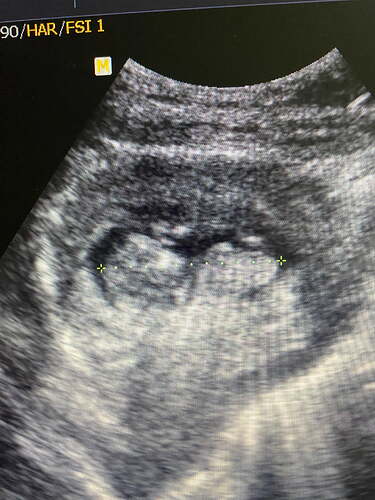

11 haftalık cinsiyet bakar musunuz

Hamilelik

IMG_8439

1920×2560 1.05 MB